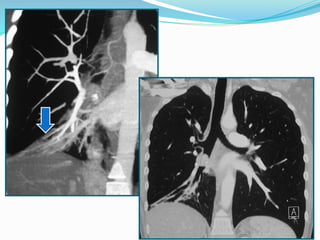

 Embolie pulmonaire.

 Affection vasculaire (embolie pulmonaire, obstruction

extrinsèque de l`artère pulmonaire : tumeur, adénopathies,

hypoplasie des artères pulmonaires ou sténose artérielle

pulmonaire).